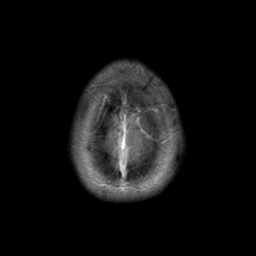

Sarcoma, MR Study #1 mr-gad -- Slice #23

[Home][Help][Clinical] Slice 23